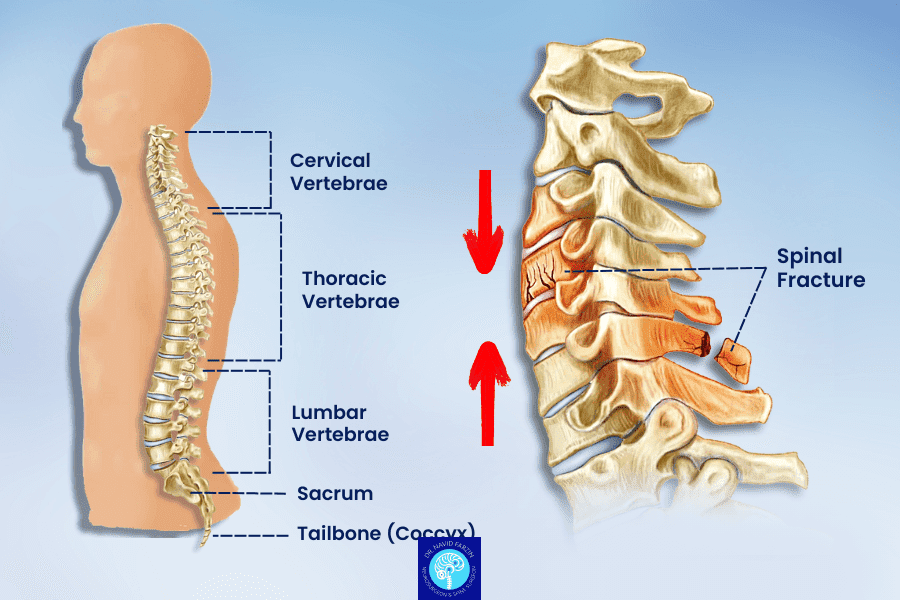

شکستگی ستون فقرات یکی از آسیبهای جدی اسکلتی–عصبی است که میتواند بر توان حرکتی، احساس اندامها و حتی عملکرد نخاع تأثیر بگذارد. به همین دلیل، انتخاب یک جراح باتجربه و متخصص ستون فقرات در شیراز برای درمان این آسیبها اهمیت بسیار زیادی دارد.

در سالهای اخیر، شیراز بهعنوان یکی از قطبهای درمانی جنوب کشور، از نظر امکانات جراحی و تکنیکهای پیشرفته ستون فقرات رشد چشمگیری داشته است. امروزه بسیاری از شکستگیهای کمری و گردنی با روشهای کمتهاجمی، لولهای، اندوسکوپی و یا فیوژن پیشرفته قابل درمان هستند.

چه زمانی جراحی شکستگی ستون فقرات ضروری است؟

در موارد زیر، جراحی سریع توصیه میشود:

شکستگی همراه با فشار روی نخاع یا اعصاب

بیحسی، ضعف یا اختلال در کنترل ادرار و مدفوع

ناپایداری مهرهها

درد شدید و مقاوم

شکستگی ناشی از پوکی استخوان که باعث تغییر شکل مهره شده باشد

تشخیص دقیق با MRI، CT Scan، معاینه عصبی و ارزیابی تخصصی انجام میشود.